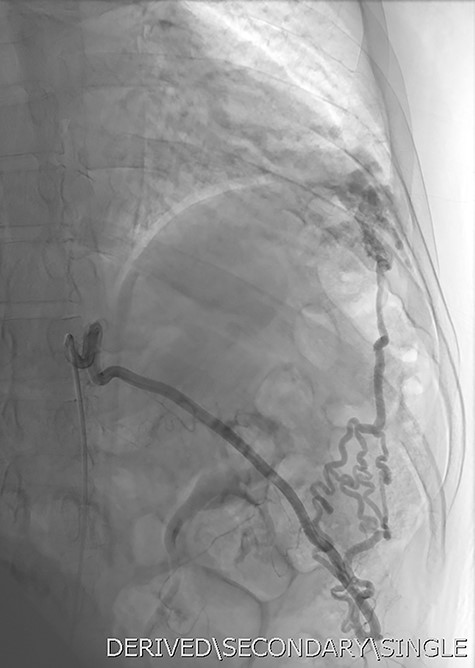

Given the findings, he was referred to Interventional Radiology for a formal digital subtraction angiogram with view of transcatheter embolization. Under local anaesthetic and sedation, a 5-french sheath was placed in the left common femoral artery. Using a 5-french pigtail catheter, aortic angiography was undertaken, confirming the CTPA findings and demonstrating predominant supply of the vascular malformation via the left intercostal arteries and the left inferior phrenic artery (Fig. 4)—draining into the left inferior pulmonary artery and vein. Superselective catheterization of the left intercostal arteries (Fig. 5) and the left inferior phrenic artery (Fig. 6) are shown. Unfortunately, due to the malformation’s volume and complexity, embolization was abandoned. He was subsequently referred to Cardiothoracic Surgery, currently awaiting consideration and workup for ligation and resection via video-assisted thoracoscopy, and potentially thoracotomy.

DSA utilizing superselective catheterization to demonstrate contribution to the PAVM via one of the many tortuous intercostal arteries.